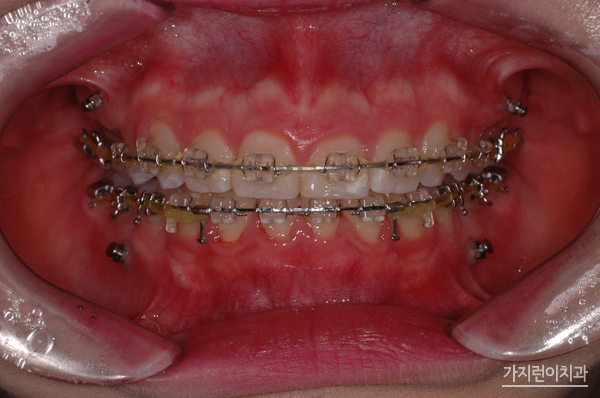

미니스크류는 인체에 해롭지 않은 나사형태로 제작된 미니 임플란트라고 보실 수 있겠습니다. 잇몸 사이 뼈에 식립해 치아를 필요한만큼 이동시키는 힘을 더하는 방식으로 치아이동을 좀 더 빠르게 도와주는 보조장치입니다. 국소마취 후 진행되기 때문에 따로 절개를 하지 않으며 출혈도 적고 통증도 적어 회복속도가 빠르다는 장점도 있습니다. 또한 잇몸이 많이 보인다거나 부분교정이 필요한는 경우 주로 사용되는데 돌출입을 해결할 때 많이 이용되고 있습니다. 이 경우 턱뼈 안에서 치아들을 뒤로 이동시키는 지지대로서의 역할을 해주기 때문에 발치교정이나 양악수술 없이도 돌출입교정에 효과적일 수 있는데요. 중요한 일정을 앞두고 있거나 직업적으로 대인관계가 중요한 서비스직종의 직장인이라면 염두해볼 수 있겠습니다.

위 환자분들의 경우 1년 8개월의 대장정 끝에 치료과정이 끝나셨습니다. 상하악의 이동을 잘 조절해 골격적인 밸런스도 마무리되셨는데요. 치아교정을 전문적으로 다루고 있는 서울가지런이치과 교정과 의원인만큼 심한 거미스마일 증상과 돌출입 증상도 무리없이 해결했답니다. 오래도록 안정된 결과를 누리고 있는 이 케이스! 걱정말고 서울가지런이치과 교정과 의원을 방문해 보시기 바랍니다.